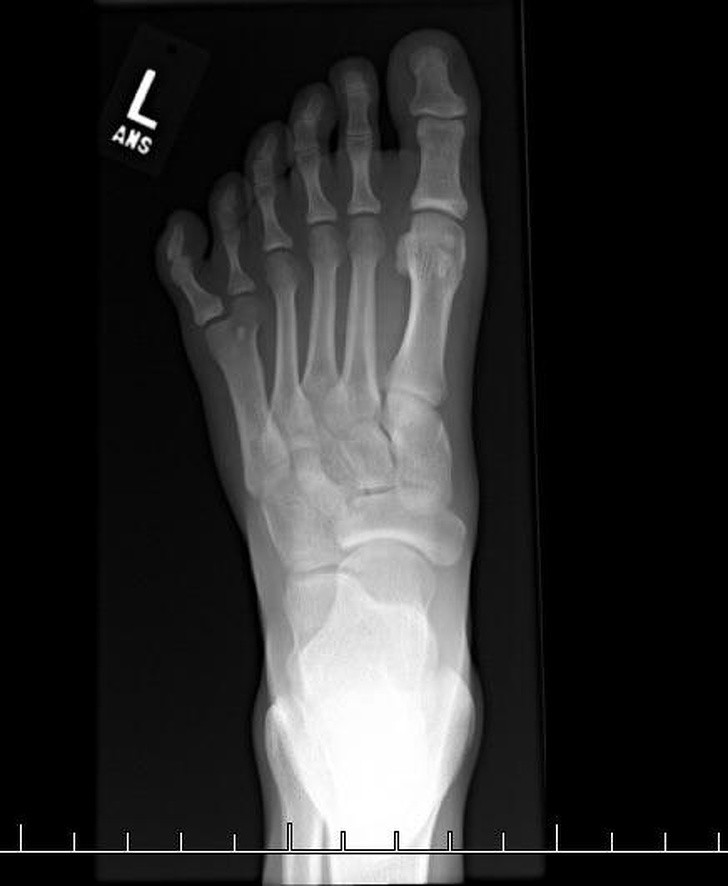

5. Một phim chụp X - quang cho thấy 1 bàn chân 6 ngón.

Ảnh: BrightSide